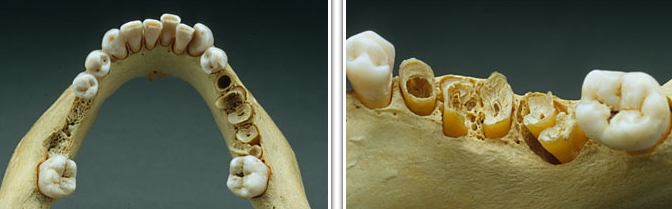

Симптомы остеопороза челюсти

Остеопороз челюсти часто протекает незаметно. В течение нескольких лет или даже десятилетий заболевание может не проявлять себя. Диагноз устанавливают, как правило, лишь после перелома челюсти и тщательного обследования для выяснения причины. По мере прогрессирования недуга кость становится пористой и хрупкой из-за длительного процесса деминерализации. Дополнительные симптомы могут включать:

- Повышенная чувствительность зубной эмали к физическим воздействиям, проявляющаяся в сильной реакции на тепло и холод.

- Увеличение подвижности зубов, что приводит к их шатанию и вызывает дискомфорт при приеме пищи.

- Уменьшение десенной ткани, в результате чего корни зубов становятся обнаженными и образуются карманы.

- Увеличение образования налета на зубах.

При появлении таких жалоб пациенты обычно обращаются к стоматологу, где проходят лечение кариеса и других стоматологических заболеваний.

| Деформация | Утончение и деформация спинки турецкого седла, видимая на рентгенограмме. Может быть асимметрия лица. | Уменьшение плотности костной ткани челюсти, хрупкость костей, повышенная чувствительность к прикосновениям. Возможно разрушение альвеолярных отростков (зубных лунок). |

| Переломы | Риск компрессионных переломов позвонков. | Повышенный риск переломов челюсти, особенно при травмах. Выпадение зубов. |